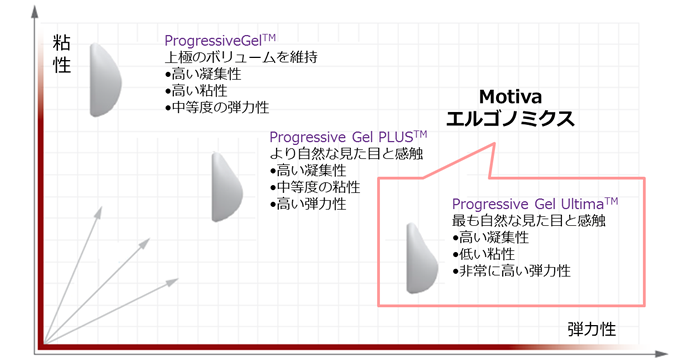

これは、シリコンが、ProgressiveGel「Ultima」に進化したことにあります。